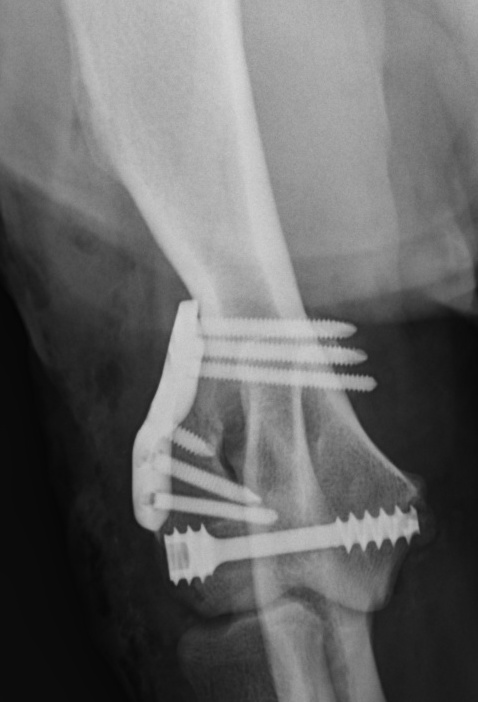

These fractures need to be re-aligned as accurately as possible, within a few days of occurring, to try and optimise elbow function in the long term. They are generally stabilised using a screw across the condyle, and a plate and screws running up the side of the bone. Sometimes, the plate is not used and more screws or a bone pin is used instead. Movement Specialist, Ben Walton, helped to design and develop a system of anatomic bone plates for humeral condylar fractures.

- How many pieces the bone is broken into. Usually, just one side of the humerus fractures off, and these fractures are more straightforward to stabilise and generally have better outcomes. Approximately 35% of condylar fractures are Y-fractures, where both sides of the humeral condyle break apart from each other and from the main shaft of the bone. These are much more difficult to stabilise.

- What implants are used. The best-available published reports suggest that complication rates are lower when plates are incorporated into the repair.